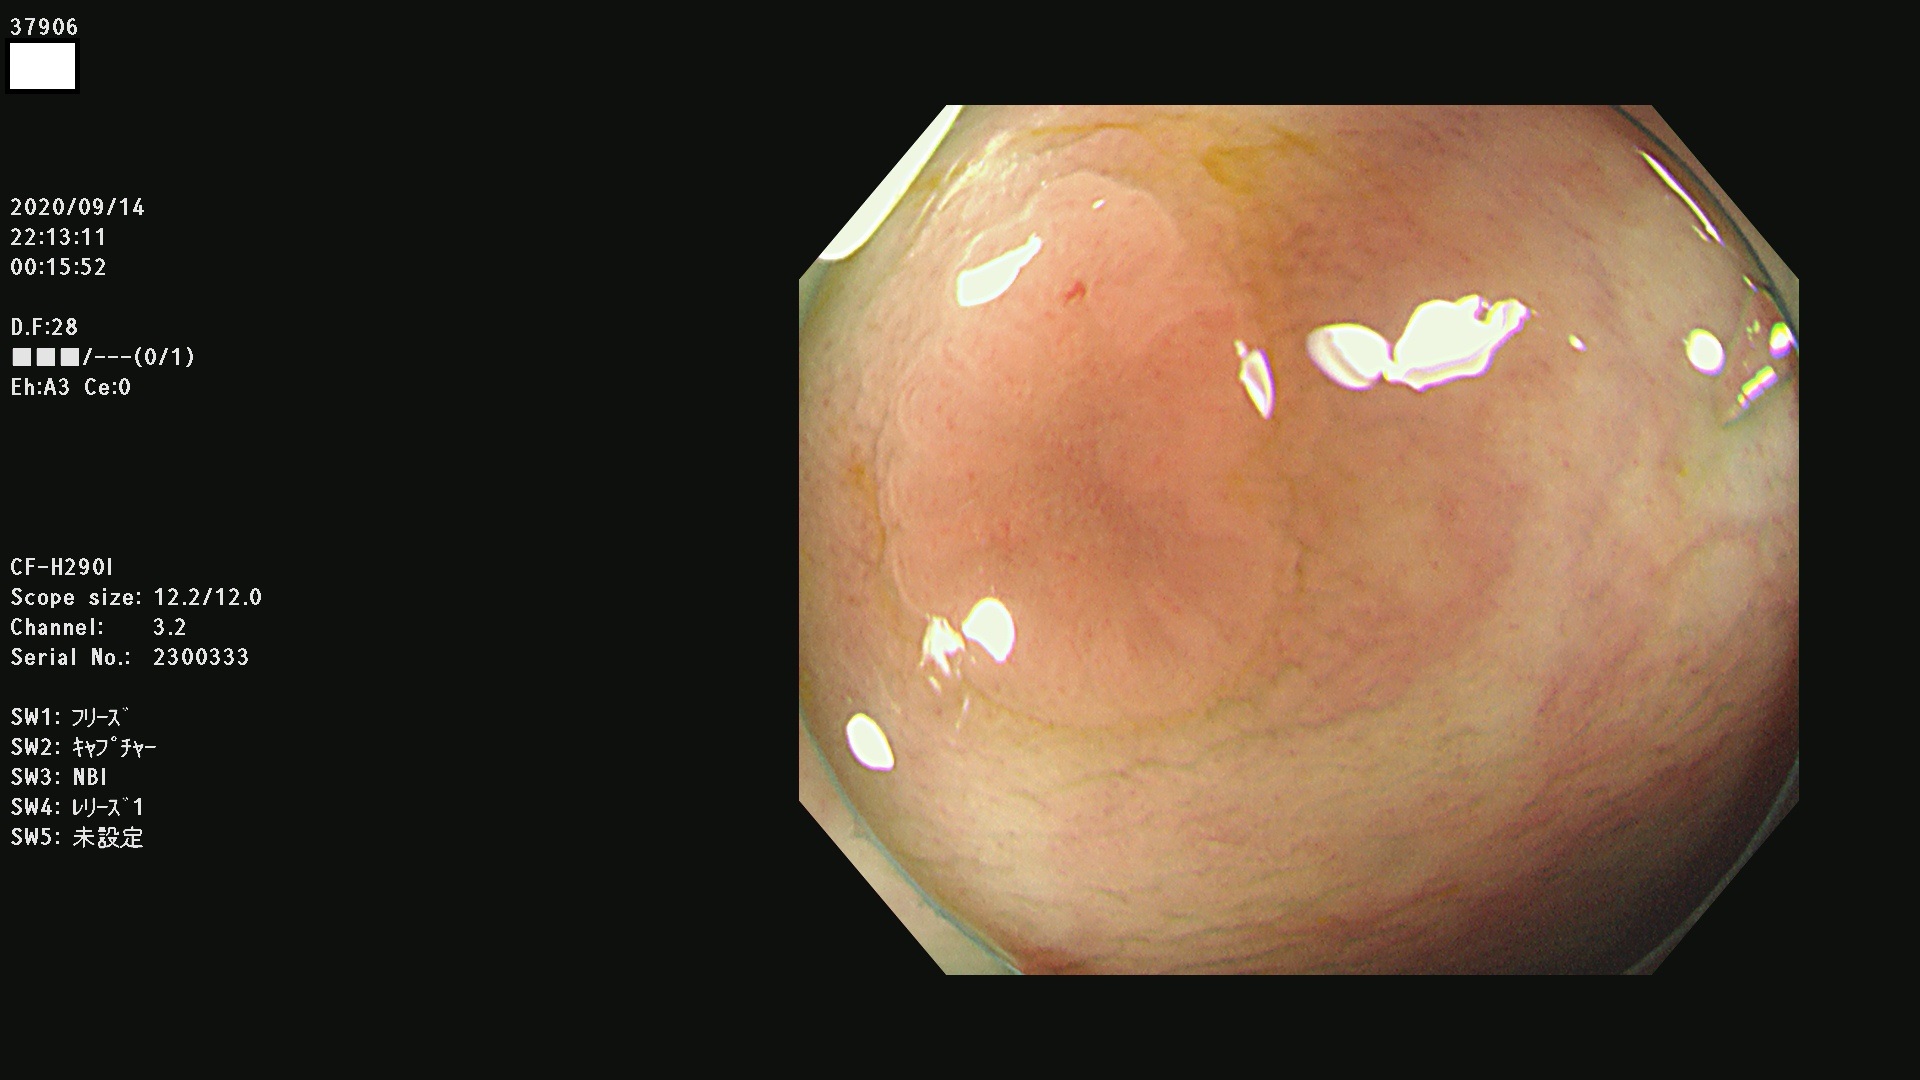

37900 37902 37903 37904 37905 37906 37907 37909 37910 37911 37912 37913 37914 37915 37916 37917 37919 37921 37922 37923 37926 37928 37929 37930 37931 37933 37934 37935 37936 37937 37938(SSAPのみ) 37939 37940 37941 37942 37943 37946 37947 37948 37949 37951 37952 37953(SSAPのみ) 37955 37956 37957(SSAPのみ) 37958(SSAPのみ) 37960 37962 37963 37964 37966 37967 37968 37971 37972 37973 37975 37976 37977 37979 37982 37983 37984 37985 37986 37987 37988 37989 37990 37991 37992 37993 37994 37995 37996 37998 37999

発見困難で危険性の高い平坦型病変(上記100名より抽出)